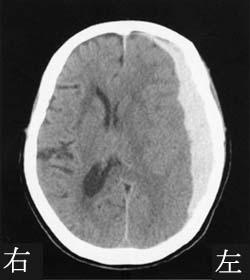

65歳の男性。右利き。突然の意識障害で搬送された。くも膜下出血の診断で、破裂脳動脈瘤のクリッピング手術を施行された。発症後3か月の頭部CTを示す。この患者に出現しやすい症状はどれか。

1

上着の左右を間違えて袖を通す。

2

ジェスチャーの模倣ができない。

3

移動する時に左側の人や物にぶつかりやすい。

4

知っている人なのに声を聞かないとわからない。

5

担当理学療法士に毎日初対面のように挨拶する。